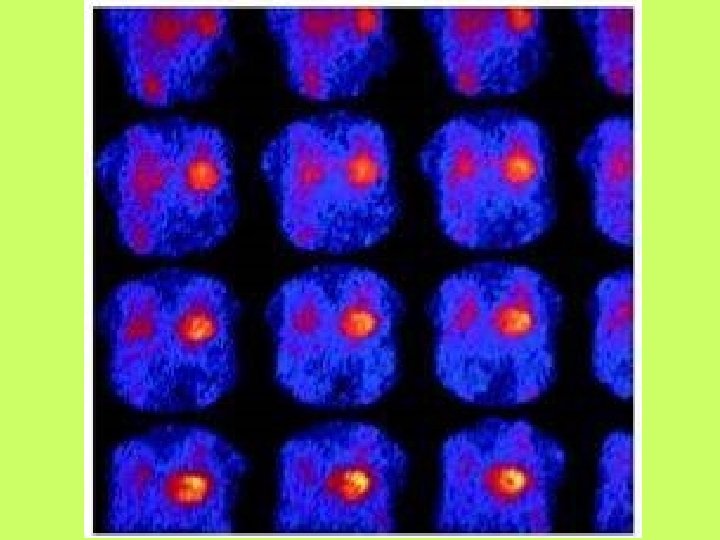

Noninvasive cardiac diagnostic studies 1 - EKG 2 -Chest X ray 3 -Exercise tolerance

Noninvasive cardiac diagnostic studies 1 - EKG 2 -Chest X ray 3 -Exercise tolerance test(ETT) 4 -Echocardiography transthoracic-trans esophagial 5 -Stress echocardiography 5 -Radionuclid imaging 6 -Cardiac catheterization